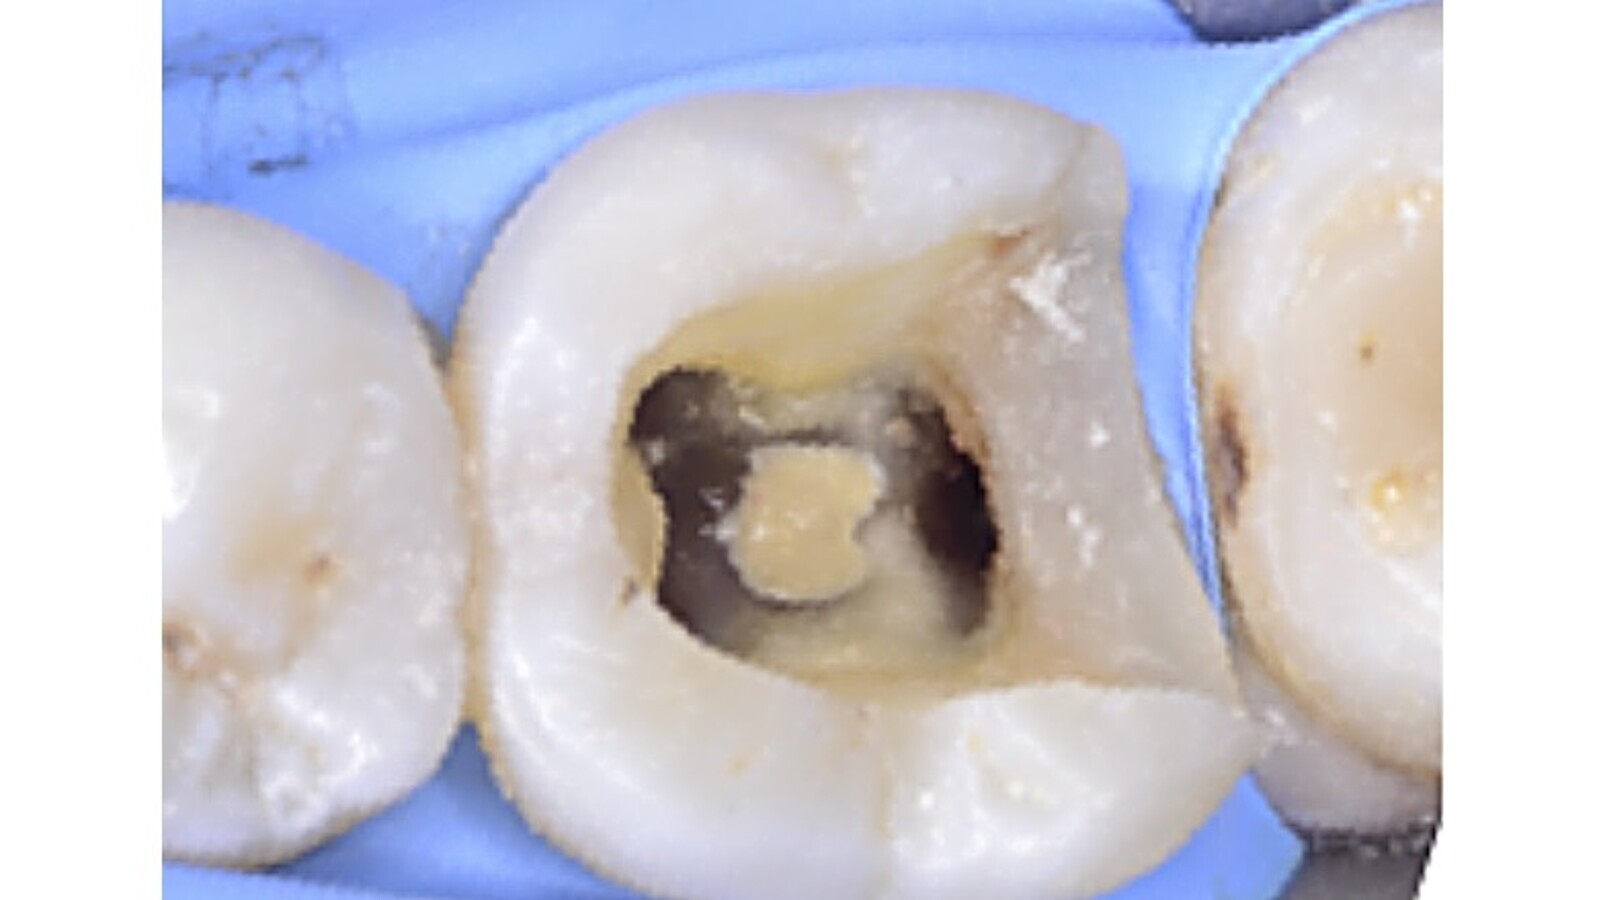

Fig. 3. Imagen clínica inicial del diente 3.6.

Fig. 4. Imagen clínica donde se puede apreciar la perforación en furca.

Fig. 5. Sellado de la perforación con Biodentine.

Durante la apertura cameral se localizó una perforación en furca que se selló con un material biocerámico.